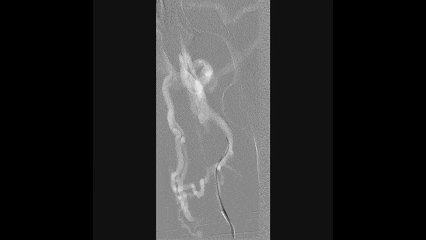

5

球囊扩张

使用4×150mm球囊扩张髂静脉段和股深静脉段

10mm球囊扩张左侧股深静脉、髂外静脉和髂总静脉

扩张后髂股静脉仍处于闭塞状态,有弹性回缩

6

支架置入

从股深静脉相对健康管腔开始

从远心端向近心端依次植入12mm支架1枚,14mm支架3枚

所有支架均为自膨式支架,近心端到达下腔静脉水平

10mm球囊对支架进行后扩